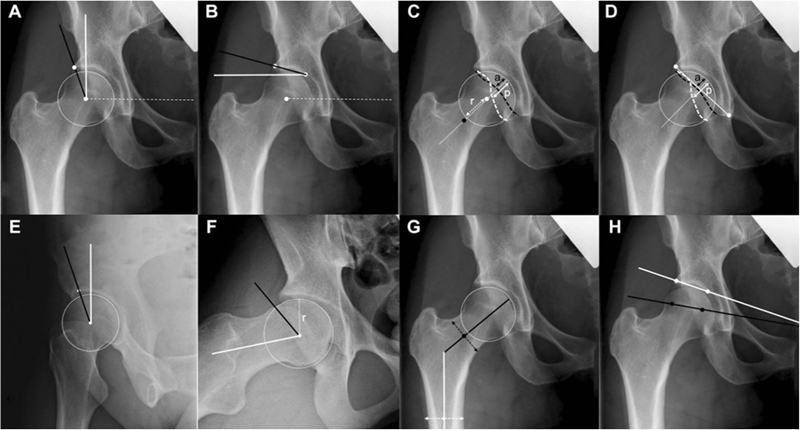

在临床评估时,应用最为普遍就是影像学评估,大部分采用X线的方式。通过X线上不同角度的表现来了解患者的髋关节稳定的状态。

通过对患者的X线指标进行评估,发现X线指标一般性特征在这三组之间没有差异。前方CE角是三种不同的状态,是有明显的差异。